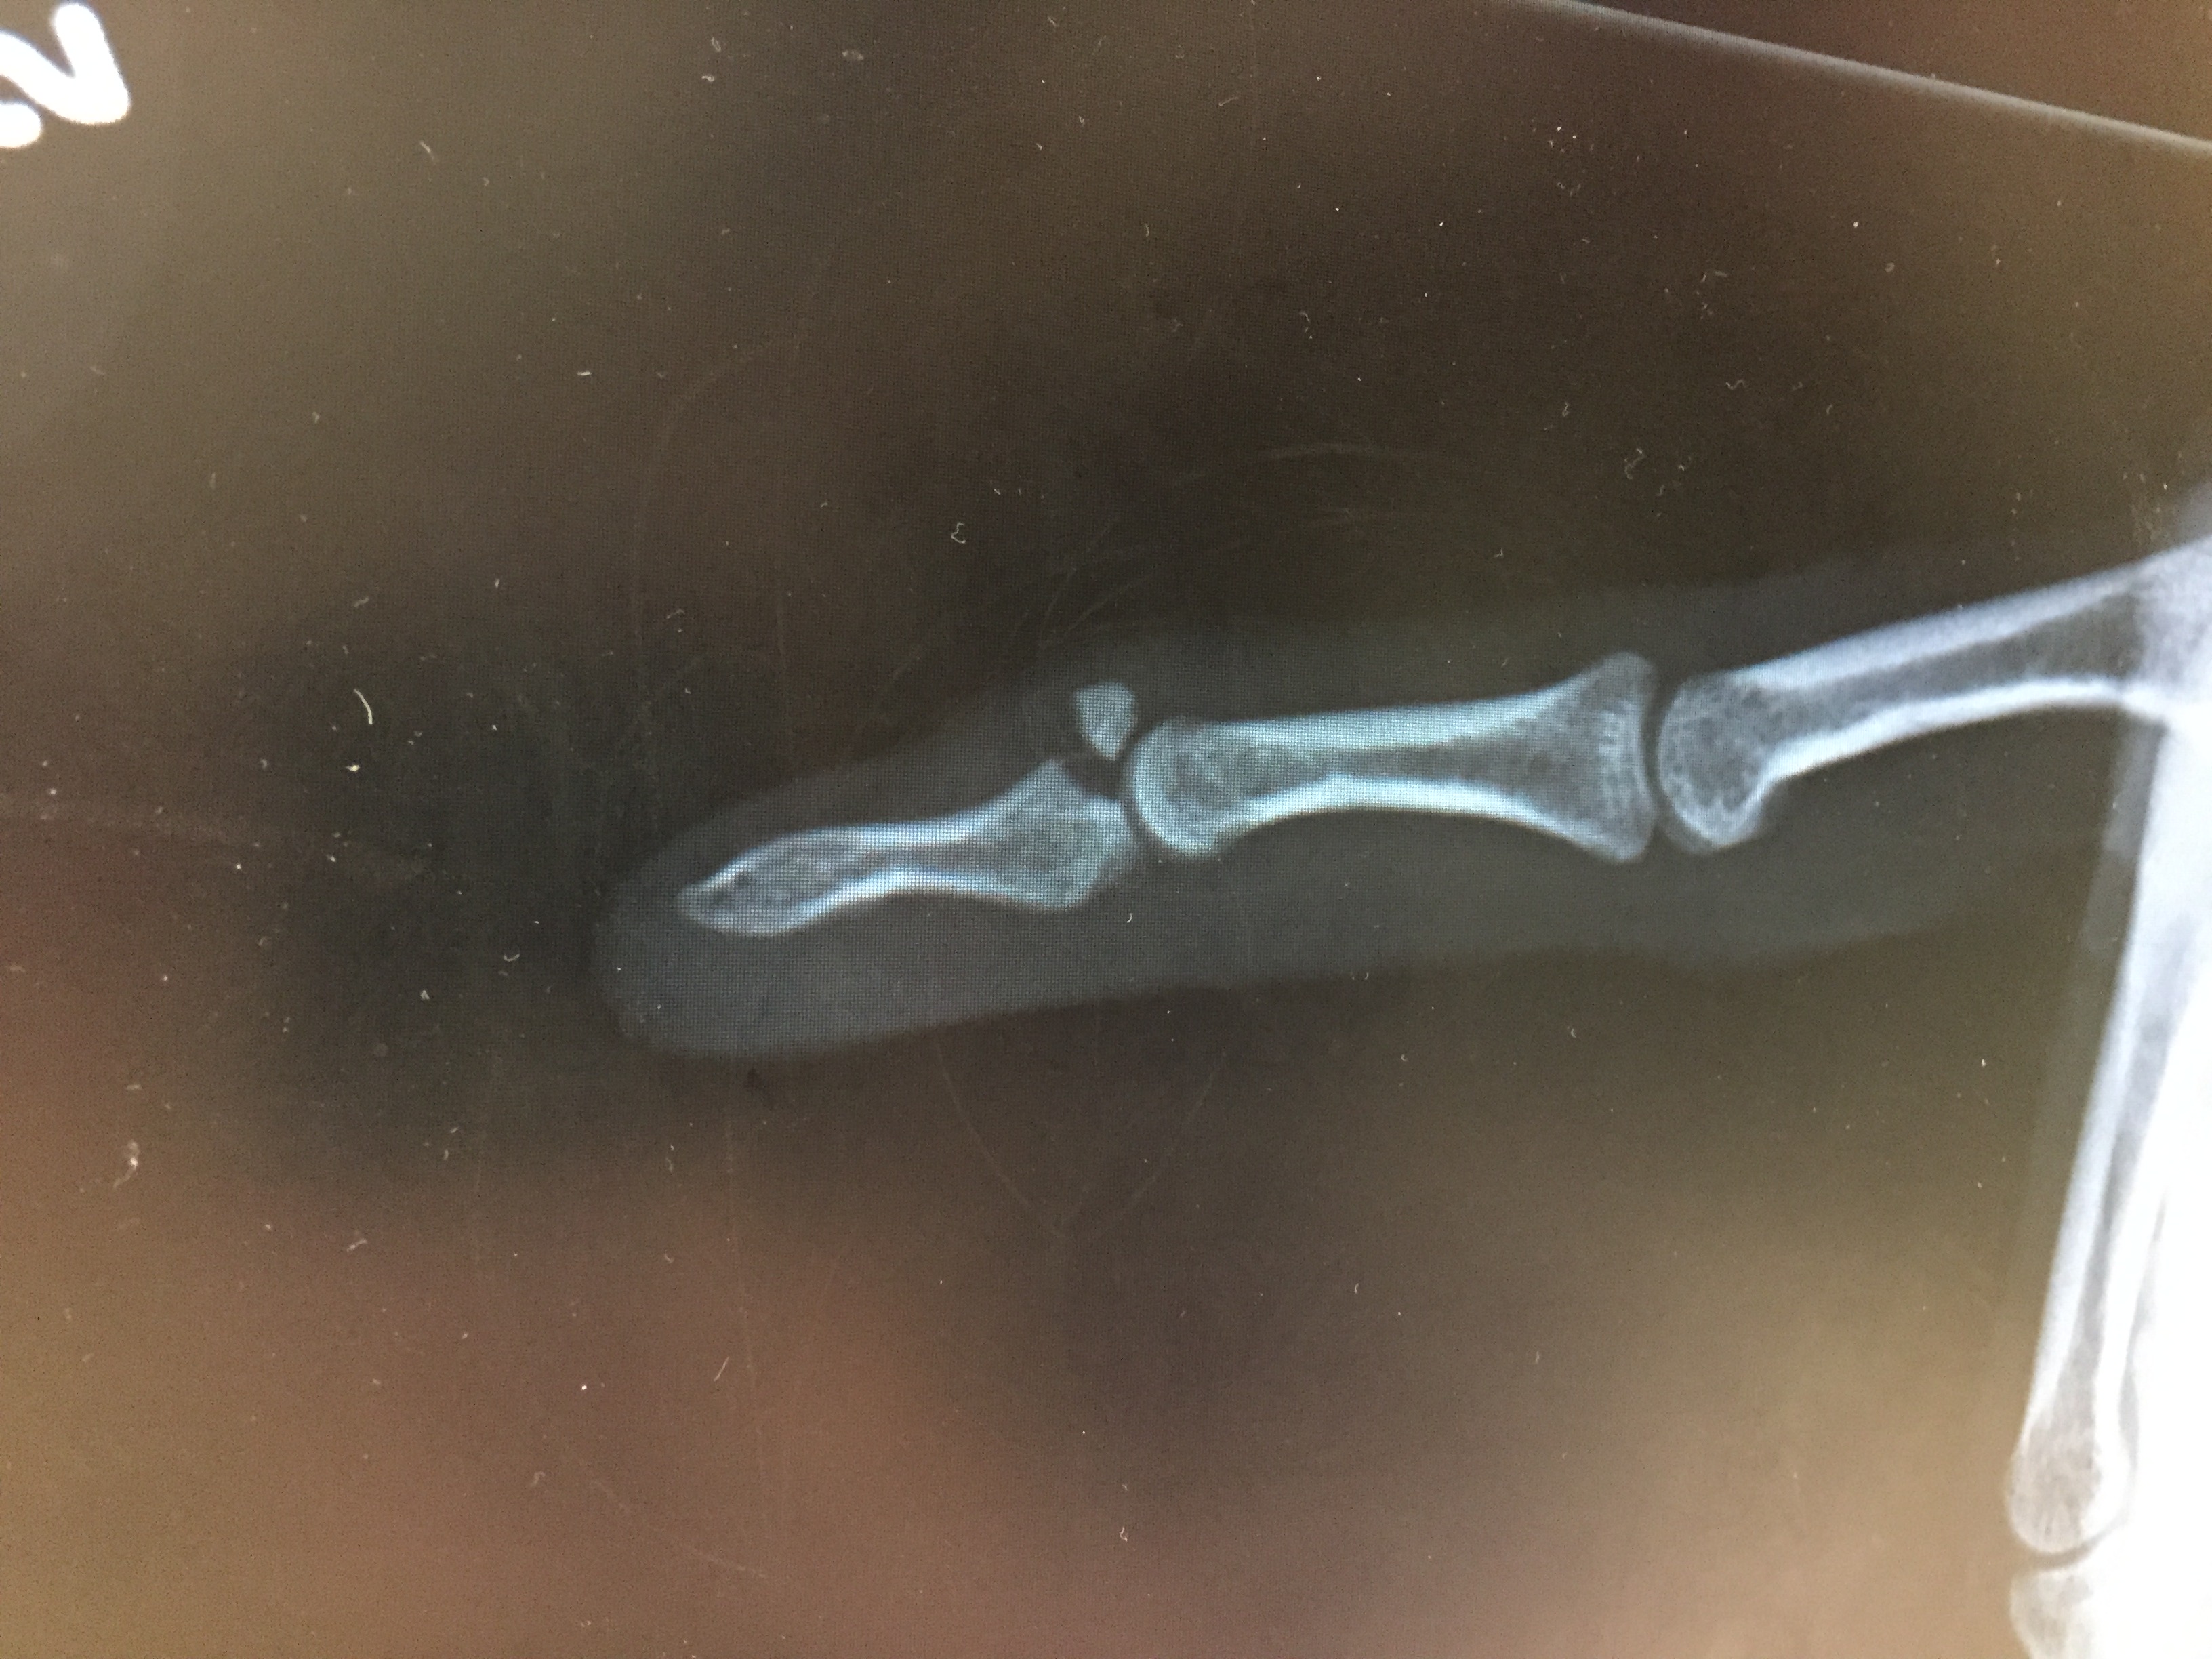

2. Bony fracture

Drop finger / extension lag of the DIPJ

- volar subluxation of distal phalanx

- fragment > 50% joint surface